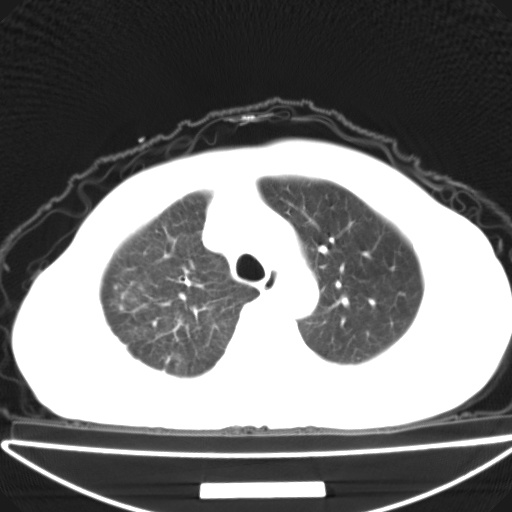

以下是引用jsgdoctor在2008-11-6 22:12:00的发言:[br]右主支气管壁明显增厚,管腔狭窄.考虑为右侧中央型肺癌伴阻塞性炎症\\肺脓肿.

以下是引用zjzjr在2008-11-6 20:25:00的发言:[br]中心型肺ca,合并阻塞性肺炎

以下是引用zsl6918在2008-11-6 19:43:00的发言:[br]右侧中心性肺癌(鳞癌)